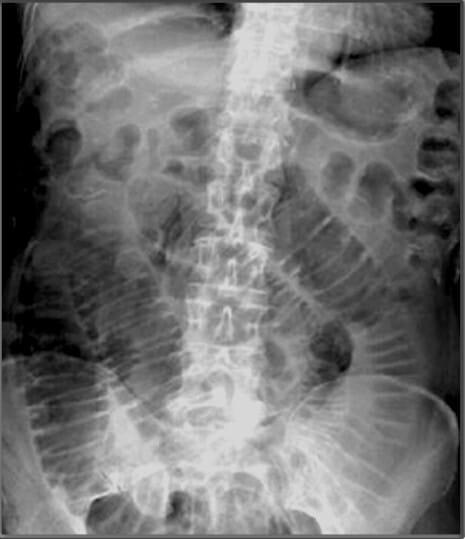

| ✅ 대장은 Haustra가 있는 넓은 장기로, AP 복부 X-ray에서 복부 주변을 따라 외측으로 분포하며, 간만곡부, 비장만곡부, S자 결장 등을 포함합니다. |

| ✅ Haustra라는 대장의 특징적인 주름 구조로, 대장의 외벽을 따라 간헐적으로 나타나는 팽창과 수축된 분절 모양입니다. AP view에서 불규칙적이고 간격이 넓은 횡선 형태로 관찰되며, 소장의 주름과 비교하여 구별하는 데 유용합니다. |

| ✅ 소장은 비교적 중심부에 위치하며, AP view에서 연속적이고 좁은 가스 음영과 함께 ‘valvulae conniventes’에 의해 가로 줄무늬가 촘촘히 나타납니다. |

| ✅ 소장의 내부 점막 주름으로, X-ray에서는 좁은 간격으로 연속된 횡선 형태를 나타냅니다. 이 구조는 소장의 대부분을 횡단하며, 대장의 Haustra와 달리 장의 전체 너비를 가로지르는 점이 특징입니다. |